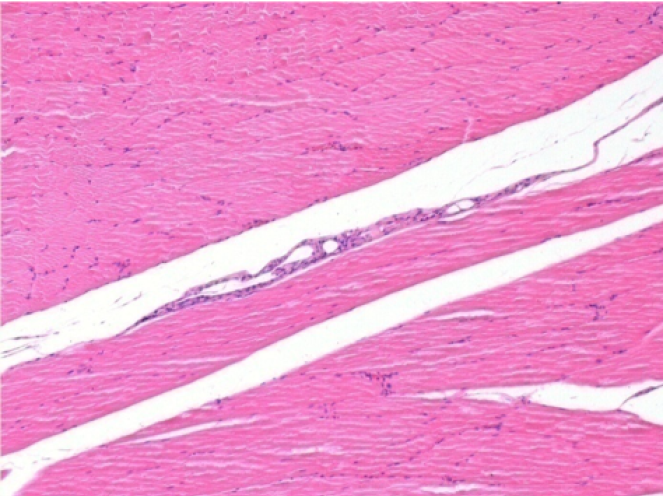

1 month after Endopeel Injection 0.1ml in the right pretibial muscle.

What is seen in black on the pictures is not a necrosis like could imagine some scientifics !

In fact, 4 conclusions have to be taken in consideration

3 months (D90)after Endopeel Injection 0.1ml in the right pretibial muscle.